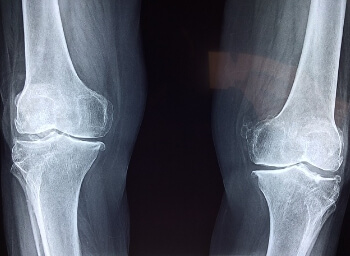

평상시에 일상생활을 하면서 무릎 관절의 중요성에 대해서 간과하는 경우가 많은데요. 나이가 들면서 무릎 관절의 통증과 활동성의 저하로 삶의 질이 떨어지고 결국은 관련된 수술을 하는 경우가 자주 있습니다. 따라서 젊었을 때부터 무릎의 관절에 대한 경각심을 갖고 잘 사용해야 할 것 같은데요. 이번 포스팅에서는 무릎 관절의 통증 원인과 뚝뚝 소리가 나는 이유에 대해서 알아보겠습니다.

무릎의 통증은 다양한 원인으로 발생됩니다. 무릎은 신테 기관중 활동성과 직접적인 관련이 있는데요. 젊은 분들도 아무런 이유 없이 무릎이 아픈 경우가 의외로 많습니다. 다양한 원인을 아래에서 확인해 보시기 바랍니다.

무릎 통증의 원인

2. 관절염

나이가 들면서 시간이 지남에 따라서 무릎 관절이 마모되고 찢어지는 손상을 입게 되면 무릎에 통증과 뻣뻣함등으로 무릎에 유연성이 감소하여 활동성이 현저하게 떨어지게 됩니다.